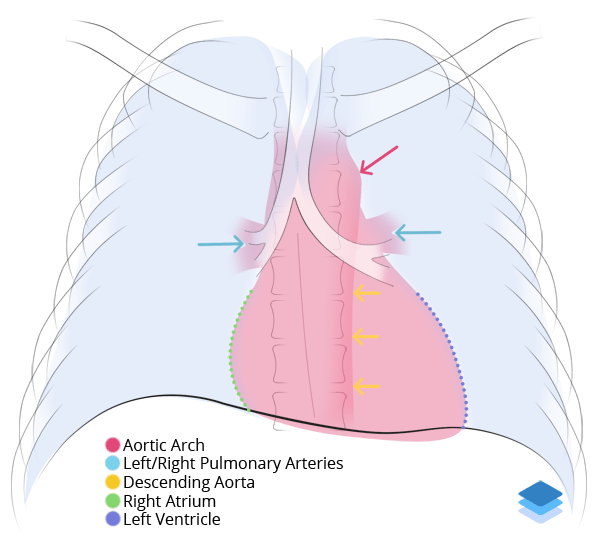

Chest

Chest

Chest radiograph & CT anatomy

Chest

Chest

Chest radiograph & CT anatomy